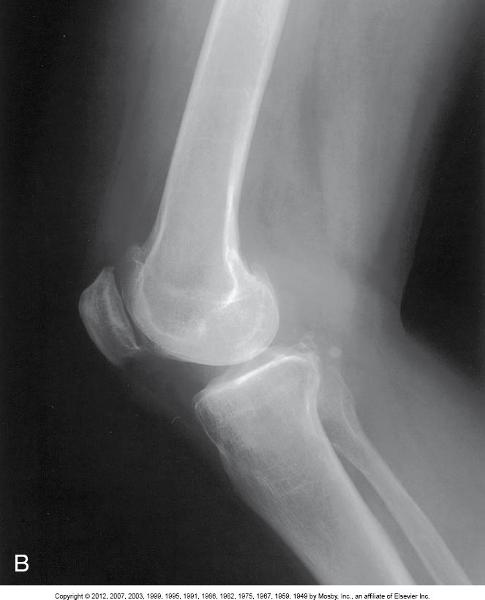

Structures Shown

• Femoral condyles

superimposed

• Open knee joint

• Patella in a lateral

profile with an open

• Soft tissue

Lateral of the Knee, Mediolateral